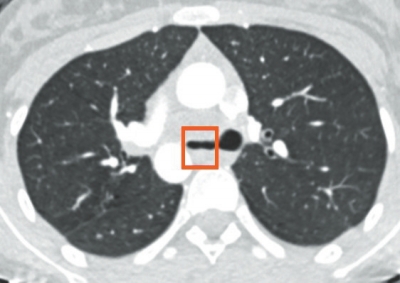

小姜确诊结核病已有一年。前不久,她被转入省内唯一的三甲呼吸疾病专科医院武汉市肺科医院治疗。检查显示,小姜的胸腔壁被病菌侵蚀、化脓,形成结核性脓胸;左主支气管周围的纵隔也被结核菌侵犯,形成脓包病灶,挤压左主气管。从CT检查片上看,左主支气管已被压得只剩一条缝。同时耐药检测也显示,小姜感染的是更难对付的耐药结核菌,常规抗结核药无法将其击退。